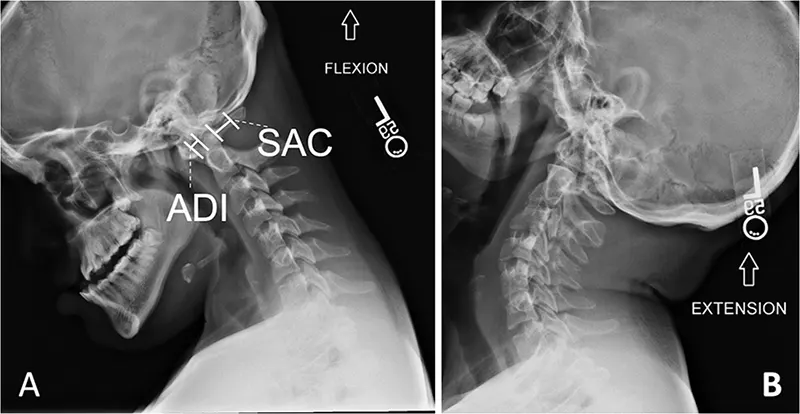

Spine X-rays can also include functional studies (dynamic views), such as flexion and extension views, particularly for the cervical and lumbar spine. These are taken while the patient bends forward and backward to assess for spinal instability, abnormal movement between vertebrae (e.g., spondylolisthesis), or limitations in range of motion. Such studies are valuable for evaluating deformities, vertebral displacements, subtle fractures, and overall segmental stability without causing excessive discomfort during the assessment of an injury.

Dynamic flexion and extension views of the lateral cervical spine are crucial for assessing ligamentous instability or abnormal motion between vertebrae, particularly after trauma or in degenerative conditions.

Cervical spine flexion and extension X-rays involve taking images while the patient actively (or sometimes passively, with caution) bends their neck forward (flexion) as far as comfortable, and then backward (extension) as far as comfortable. These dynamic views are particularly useful for evaluating suspected neck injuries or ligamentous instability. Common reasons a doctor might order these views include:

- Assessment of Whiplash Injury or other ligamentous injuries: To assess potential damage to ligaments or intervertebral joints resulting from sudden neck movements (acceleration-deceleration injuries).

- Detection of Cervical Instability: To detect abnormal or excessive movement between vertebrae, which can occur in conditions like rheumatoid arthritis, Down syndrome, certain congenital anomalies, or following trauma.

- Evaluation of Degenerative Disc Disease or Spondylosis: To identify if abnormal motion or malalignment contributes to pain or neurological symptoms caused by wear and tear on the cervical spine.

- Post-Surgery Evaluation: To check the stability of the spine after previous cervical fusion surgery or other spinal operations.

- Trauma Assessment: To evaluate for subtle fractures, subluxations, or ligamentous injuries after head or neck trauma, especially if static X-rays are inconclusive but clinical suspicion remains.

The decision to utilize flexion and extension views is based on the individual patient's clinical situation, symptoms, and the findings of initial static X-rays, and will be determined by the healthcare provider. These views are contraindicated if a grossly unstable fracture is already identified or strongly suspected.